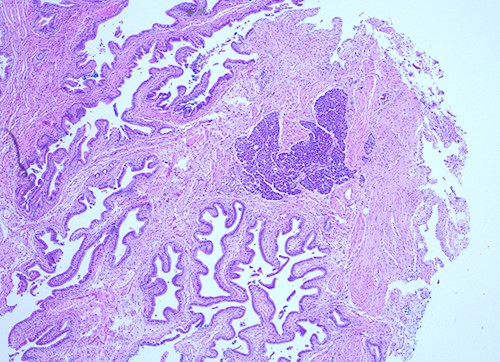

She proceeded to an elective laparoscopic cholecystectomy. At the time of her procedure, she was found to have features suggestive of chronic cholecystitis with peritoneal adhesions. Her procedure was straightforward and intraoperative cholangiogram showed a spiral cystic duct with the trifurcation of intrahepatic ducts. Her common bile duct appeared mildly dilated however tapered at the lower end and showed filling of the duodenum with no filling defects. The histology from the gallbladder showed variable fibromuscular thickening of the wall with intramural cystic Rokitansky-Aschoff sinuses, but no significant inflammation. Focal ectopic pancreatic acinar tissue (1 mm) within the gallbladder was found (Figs 1–3). There was no evidence of intestinal metaplasia, dysplasia or malignancy.

Histological examination of gallbladder ×20 showing island of ectopic pancreatic tissue adjacent to the mucosa of the gallbladder neck.